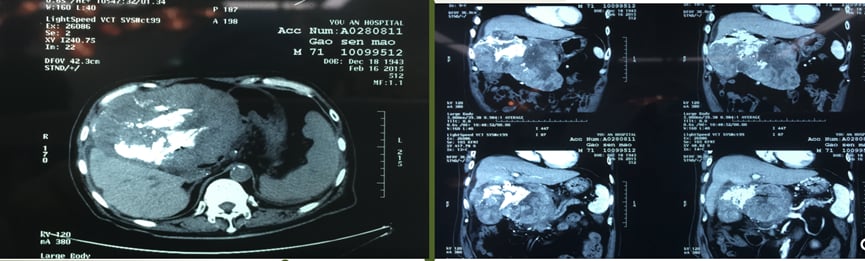

在外科医生眼中,影像学报告中的肿瘤大小、个数、侵犯范围以及与大血管的关系是决定能否手术、如何手术的关键信息。例如,大的单中心肿瘤如果恶性程度较低,通常会优先考虑切除;而多个肿瘤可能需要根据其分布和起源(单中心转移或多中心发生)来决定是消融、微创切除还是肝移植。